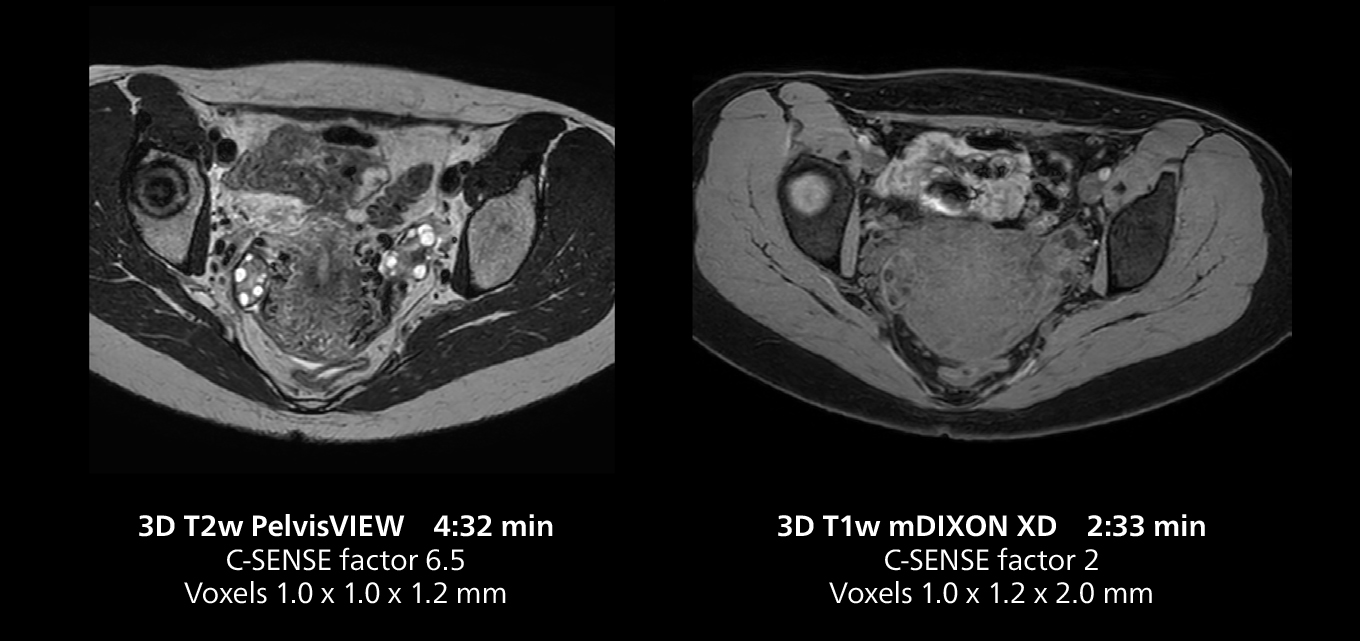

Dr. Gellée highlights the robust free-breathing scans as “the feature that makes the biggest difference in my daily work. The 3D free breathing sequences are very reproducible, and the axial acquisition is very good. For example, in endometriosis, which is one of my focus areas, it provides high contrast and good resolution so that I can see small details. We also use free breathing for liver and pancreas imaging. In multi-phase liver studies, 4D Free Breathing delivers 3-second temporal resolution, making a dynamic scan with more than one arterial phase possible.”

The MR 5300 with Compressed SENSE is up to 50%** faster for many exams. It can provide routine exams in less than 5 minutes and whole-body exams in less than 20 minutes. Saint-Augustin has taken advantage of that speed to create highly efficient protocols. The hospital’s standard stroke protocol is just about 8 minutes, and standard ENT, prostate PIRADS staging, and endometriosis studies all clock in at just about 10 minutes.***

“We have more speed in 3D sequences,” Dr. Gellée states. “With Compressed SENSE, we can replace two or three 2D scans withone high-quality 3D scan. High quality additional orientations are then obtained by post-processing of the 3D data set, thus saving scanning time.”